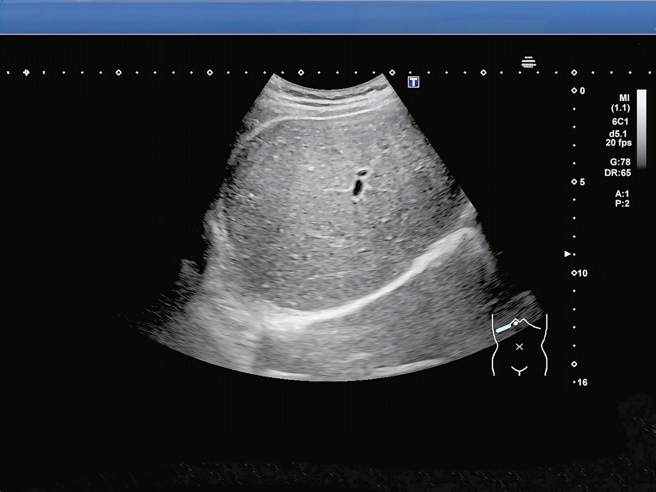

Theo bác sĩ, nam sinh được gia đình đưa đến bệnh viện cấp cứu trong tình trạng đau bụng dữ dội. Kết quả khám cho thấy bệnh nhi bị béo phì, viêm dạ dày cấp tính. Kết quả siêu âm cho thấy gan của nam sinh trắng xóa. Bệnh nhi được chẩn đoán mắc gan nhiễm mỡ nặng.

Gan của nam sinh trắng xóa. (Ảnh: China Times)